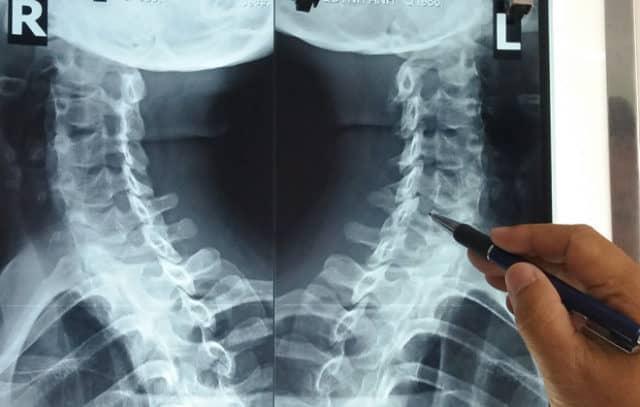

Những kỹ thuật y tế nào dùng để chẩn đoán thoái hóa đốt sống cổ?

Ngoài ra, bác sĩ còn có thể thực hiện các xét nghiệm hình ảnh hoặc kiểm tra chức năng thần kinh khác để xác định chẩn đoán:

- Xét nghiệm hình ảnh: Bao gồm chụp X-quang vùng cổ, chụp cắt lớp (CT), chụp cộng hưởng từ (MRI) hoặc chụp tủy cổ cản quang để quan sát hình ảnh thoái hóa đốt sống cổ (nếu có).